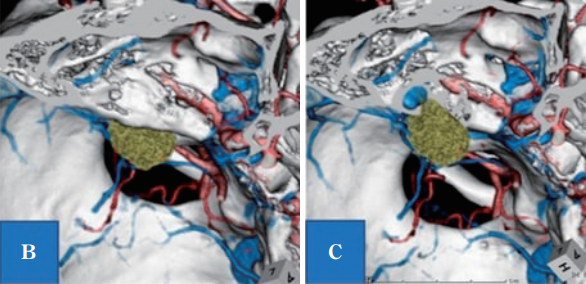

术前头颅CTA发现关键解剖变异,左侧颈静脉球高位。且颈静脉球紧贴内听道后方壁,导致该处骨质缺损。肿瘤位于内听道前上方。

B:计算机断层扫描-骨骼血管造影(CTA)显示,左上前侧有肿瘤(绿色肿块是增强区域);C:B所示的IAC壁骨缺失,显示颈高球非常靠近内听道和肿瘤。